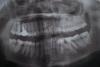

neth Опубликовано 17 мая, 2012 Автор Поделиться Опубликовано 17 мая, 2012 да еще конкретно об одном зубебыл хронический гангренозый пульпит. все ли нормально по снимку?прошло чуть больше месяца после пломбировкинерв удаляли сначала пастой, но через 3 дня начались боли, поставили крезофен, но боль не уменьшалась. после пломбировки боль уменьшилась, но иногда начал ныть после твердой пищи.7 нижний зуб слева. буду очень признательна! зубы совсем покоя не дают Ссылка на комментарий

Мартовский Опубликовано 17 мая, 2012 Поделиться Опубликовано 17 мая, 2012 Судя по этому снимку, каналы запломбированы хорошо, может боли и пройдут.Что же до всего остального, то только по панорамнику нельзя план лечения составить, но даже по нему видно, что не только беременность виновата. Надо прикус исправлять, создавать нормальные условия для функционирования и очистки зубов, а иначе быстро свои зубы порастеряете. 1 Ссылка на комментарий